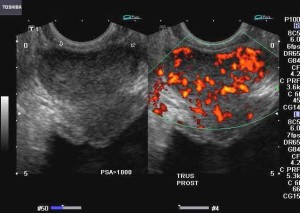

Presto un semplice esame delle urine potrebbe rivelare quale sia il trattamento migliore per ogni singolo paziente affetto da tumore...

La notizia della scoperta del nuovo metodo, messo a punto e brevettato dal Mayer, è stata pubblicata sull'autorevole rivista internazionale...